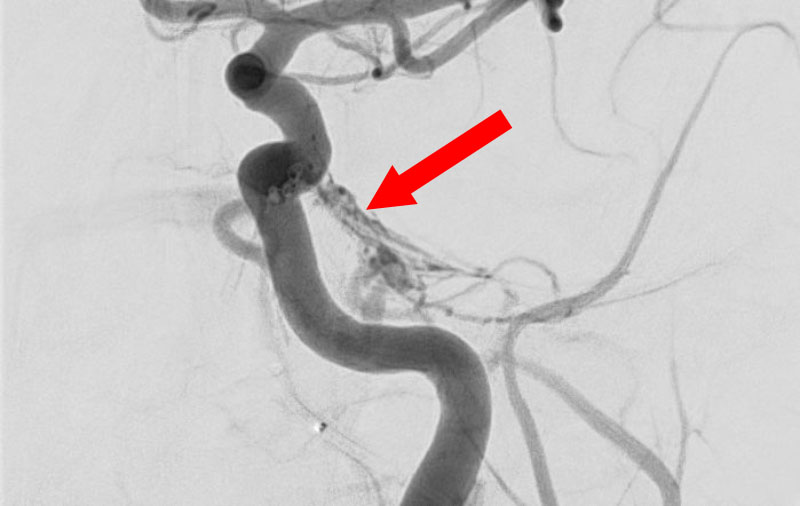

No.1481 手術前

No.1481 手術中

No.1481 手術後

脳動静脈奇形

20代

兵庫県の病院